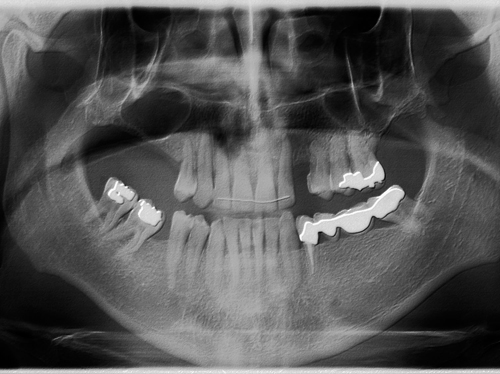

También se le sustituya el puente de la mandíbula que presentaba movilidad debido a caries en los dientes pilares por dos implantes y se le coloca otro implante en un canino superior ausente.

Después de 17 años los implantes siguen estables y sanos. Félix tiene una sonrisa completa y una boca sana, y nos cuenta que va tan bien que no distingue entre sus dientes naturales y los implantes.